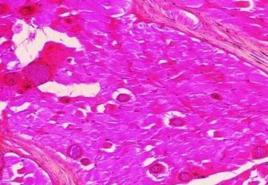

2.病理剖檢:在肌肉組織中發現特異性包囊即可確診。肉眼可見到與肌纖維平行的白色帶狀包囊。製作塗片時可取病變肌肉組織壓碎,在顯微鏡下檢查香蕉形的慢殖子,也可用姬氏液染色後觀察。做切片時,可見到住肉孢子蟲包囊壁上有輻射狀棘突,包囊中有中隔。

豬住肉孢住子蟲病肌肉中寄生的蟲體切片